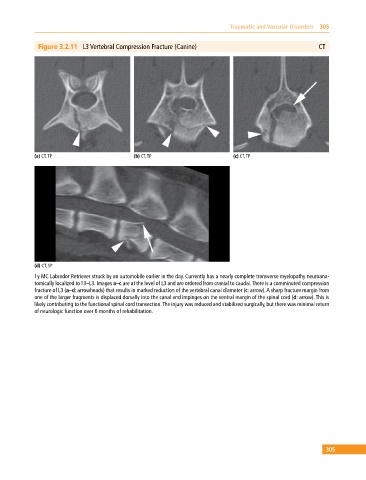

Figure 3.2.11 L3 Vertebral Compression Fracture (Canine) CT

(a) CT, TP (b) CT, TP (c) CT, TP

(d) CT, SP

1y MC Labrador Retriever struck by an automobile earlier in the day. Currently has a nearly complete transverse myelopathy neuroana-

tomically localized to T3–L3. Images a–c are at the level of L3 and are ordered from cranial to caudal. There is a comminuted compression

fracture of L3 (a–d: arrowheads) that results in marked reduction of the vertebral canal diameter (c: arrow). A sharp fracture margin from

one of the larger fragments is displaced dorsally into the canal and impinges on the ventral margin of the spinal cord (d: arrow). This is

likely contributing to the functional spinal cord transection. The injury was reduced and stabilized surgically, but there was minimal return

of neurologic function over 6 months of rehabilitation.